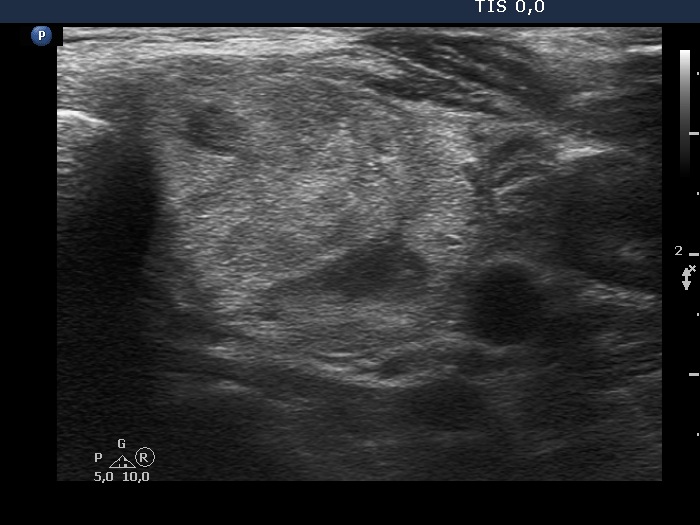

Ultrasonography. The thyroid was echonormal. There was an almost completely cyst in the right lobe. The left lobe was composed of a nodular area composed of multiple discrete lesions. The largest diameter of the nodular mass has increased from 15 mm to 37 mm in the last seven years. The size of the left lobe was 30x20x49 mm 7 years ago while the diameters were 39x23x58 mm at the present examination.